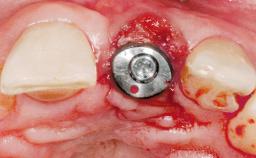

Placement Protocol Immediate implant placement

Socket Morphology Single-root socket

Socket Integrity Sufficient, with intact bone walls

Bone Volume Sufficient, with intact walls